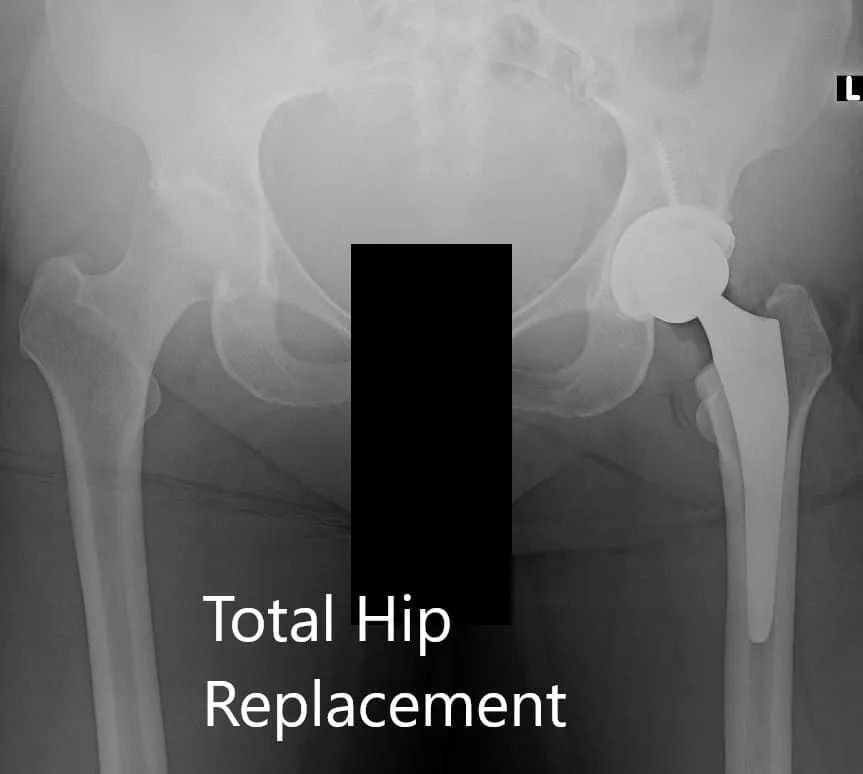

Radiografía postoperatoria de la pelvis que muestra visión AP y lateral

Implante utilizado: Carcasa acetabular de 60 mm con tornillo cancelloso de 6,5 mm x 30 mm, cabeza femoral cerámica de 36 mm, polietileno de 0 grados y talla de cadera de ángulo de cuello de 127 grados.